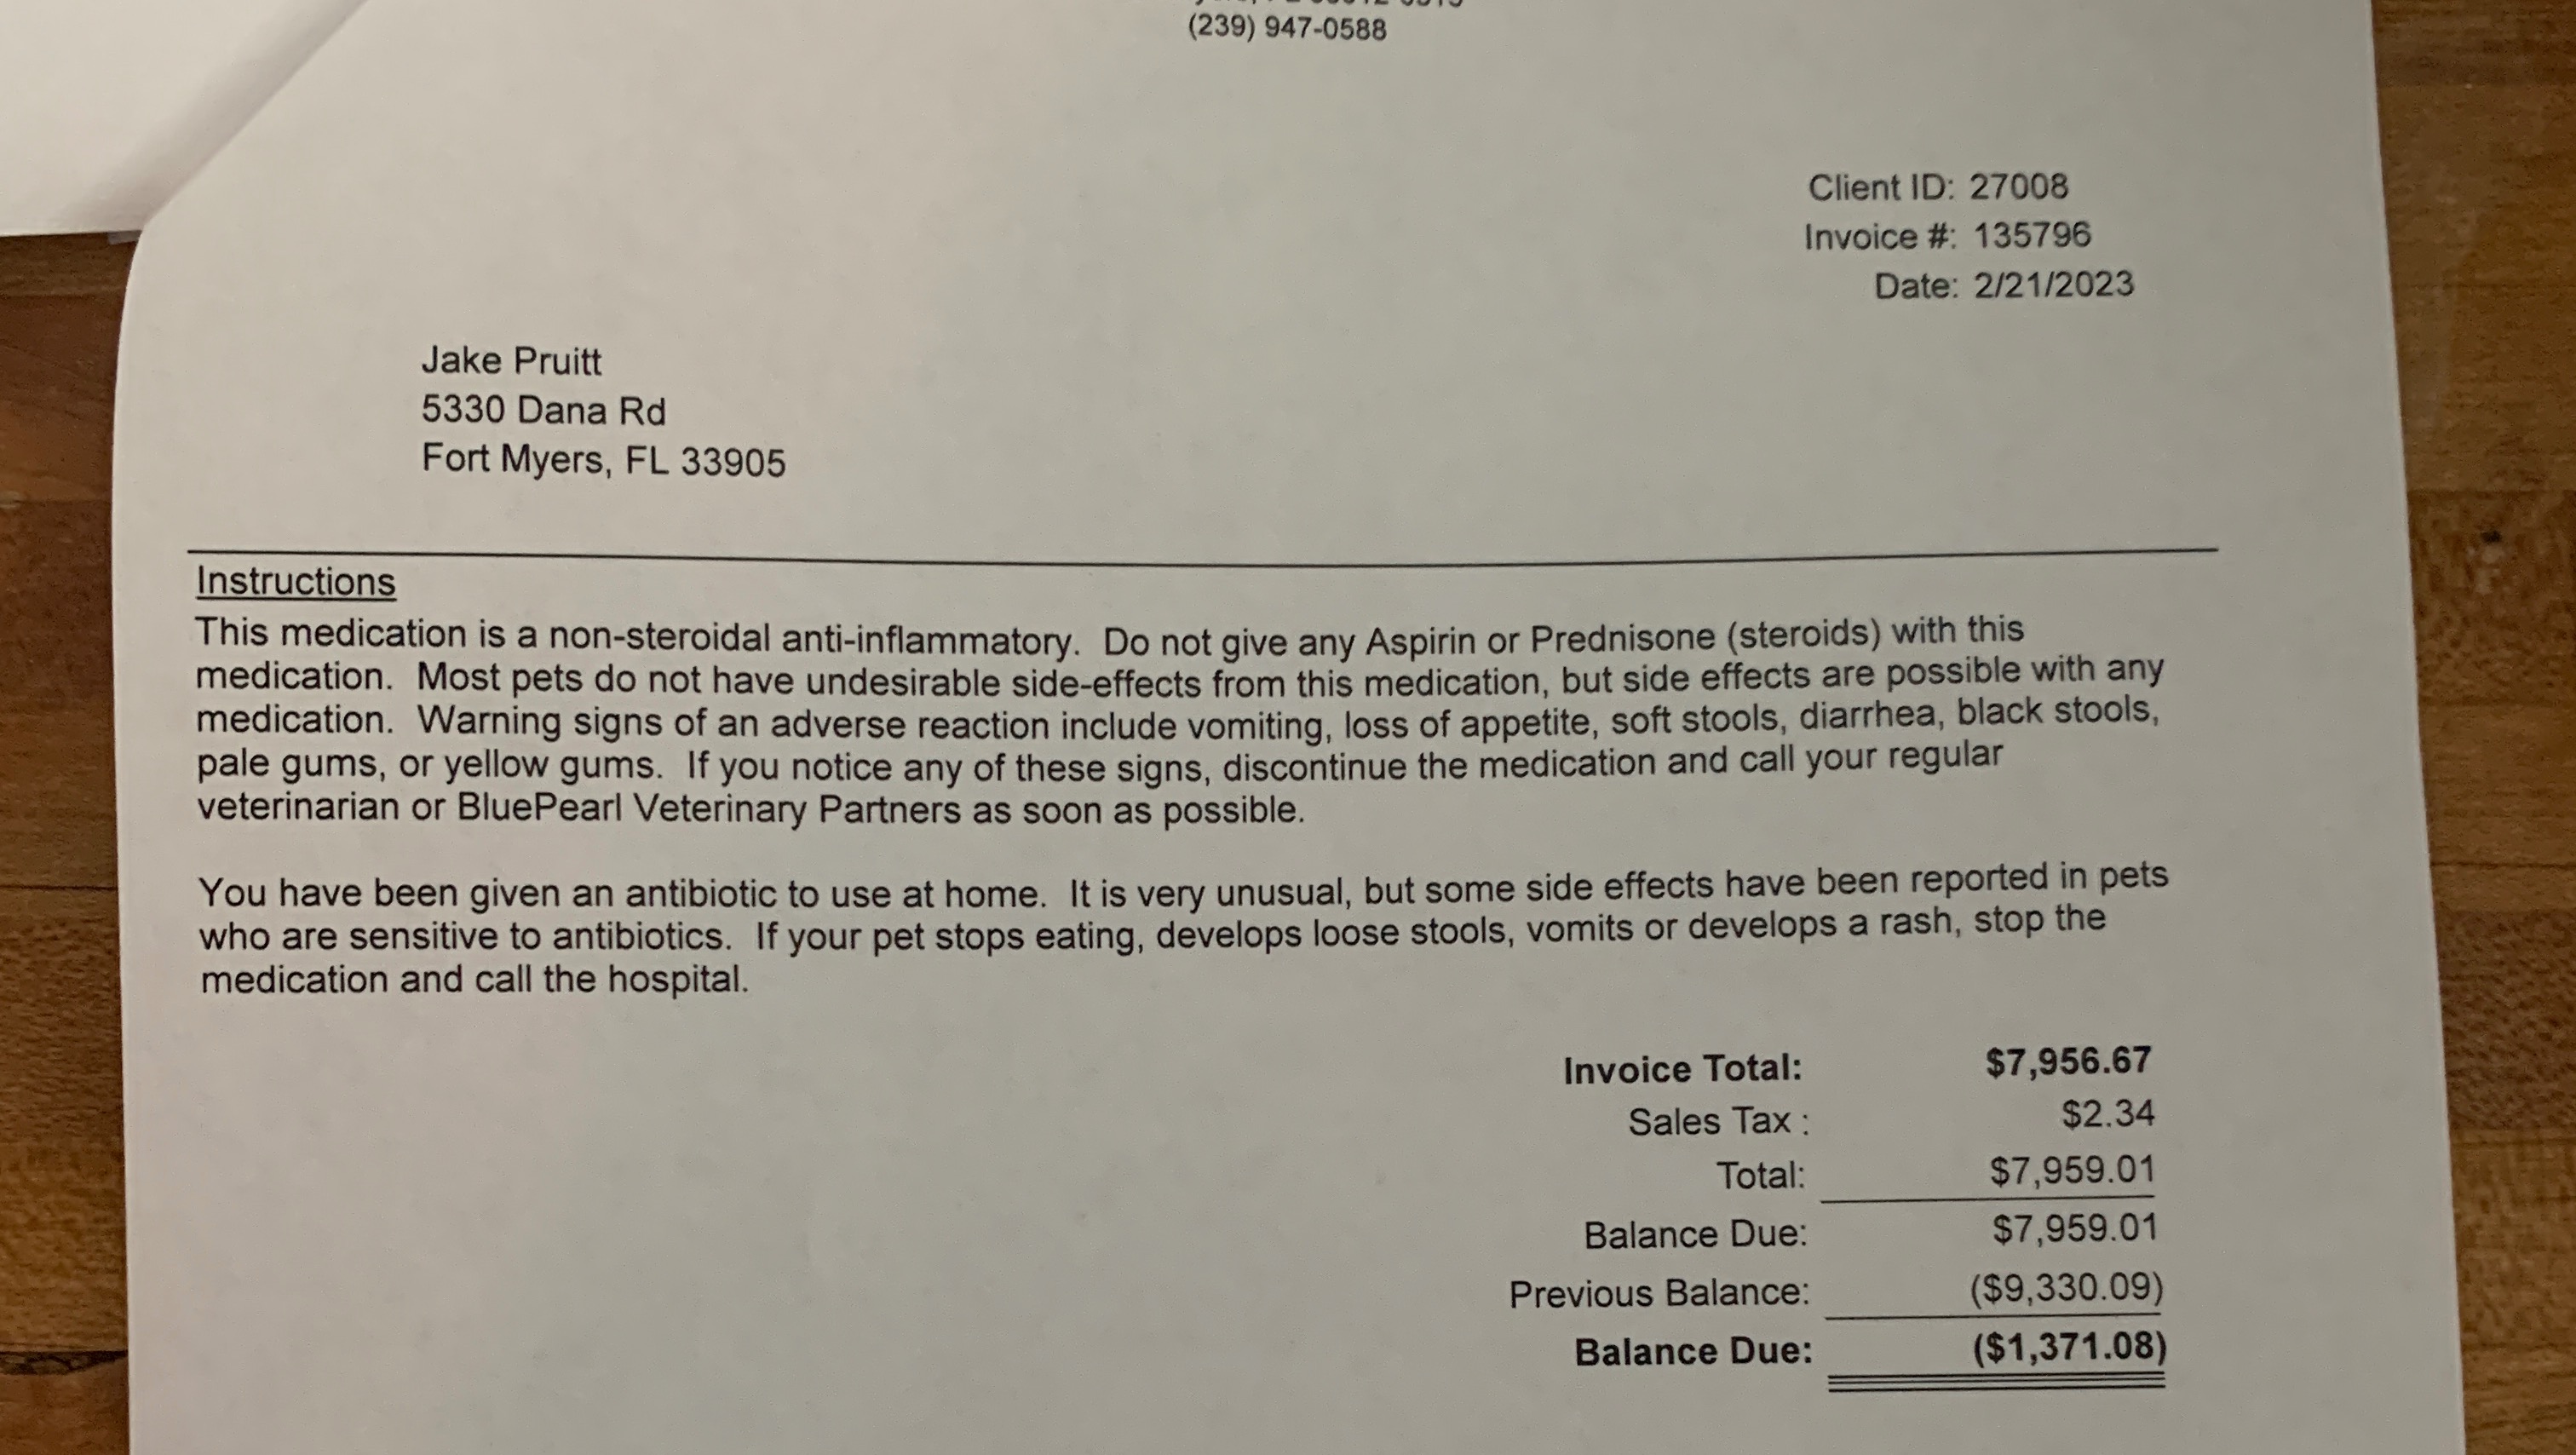

Considering the enormity of his bills, ($7,956.67 was the cost of his initial surgery), it was ultimately the best outcome and the only way we were guaranteed to recoup any funds. Enforcing a judgment is not an easy process, from what we understand.